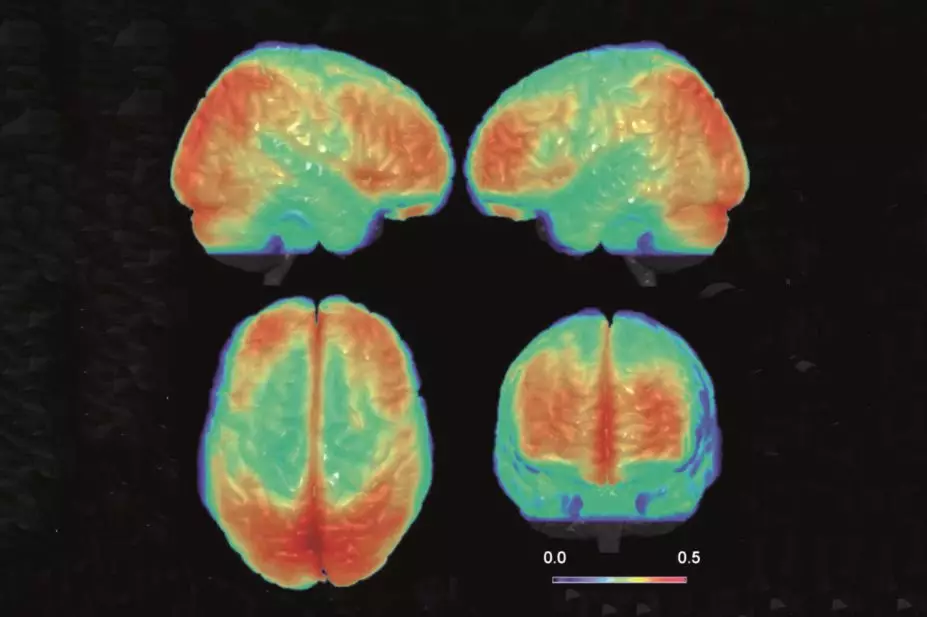

/ BIPOLAR IS A MEDICAL CONDITION OF THE BRAIN

/ & SHULD BE TREATED AS SUSCH

/ REMOVE THE STIGMA AGAINST MENTAL HEALTH SITUATIONS FROM UR BRAINS